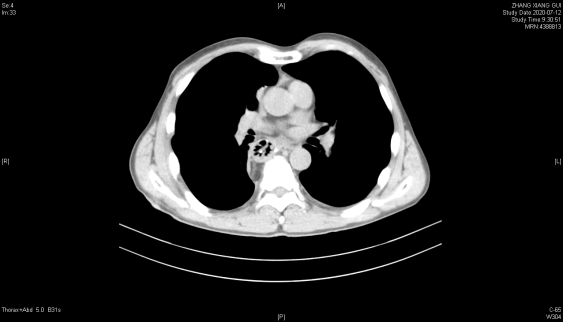

联合治疗2周后胸部增强CT:食管中段管壁增厚,增强扫描呈较明显不均匀强化,较前好转,胸廓入口水平气管右侧见肿大淋巴结,明显不均匀强化,较前减小。

2020年6月24日 联合治疗2周期后胃镜(上)和胸部增强CT(下)

2020年7月12日 术后2周复查胸部CT